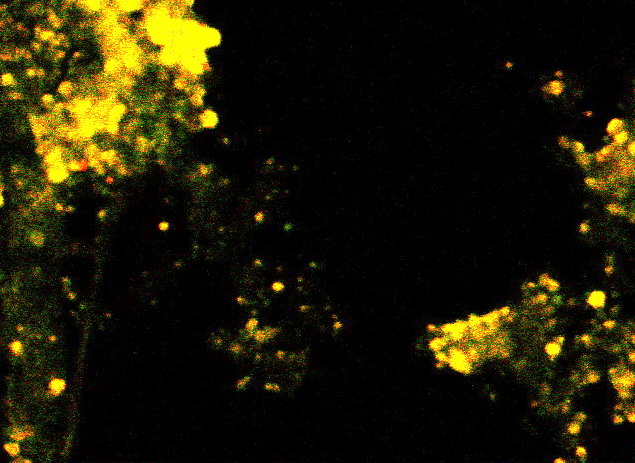

photo :: strawberry pie